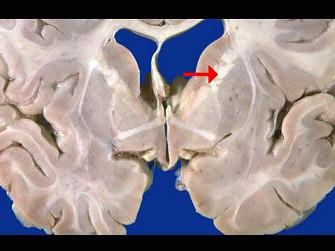

问题 如图箭头所示为大脑哪个部位 ( )

选项 A、内囊 B、齿状核 C、丘脑 D、尾状核 E、壳核 一、单项选择题

答案 A